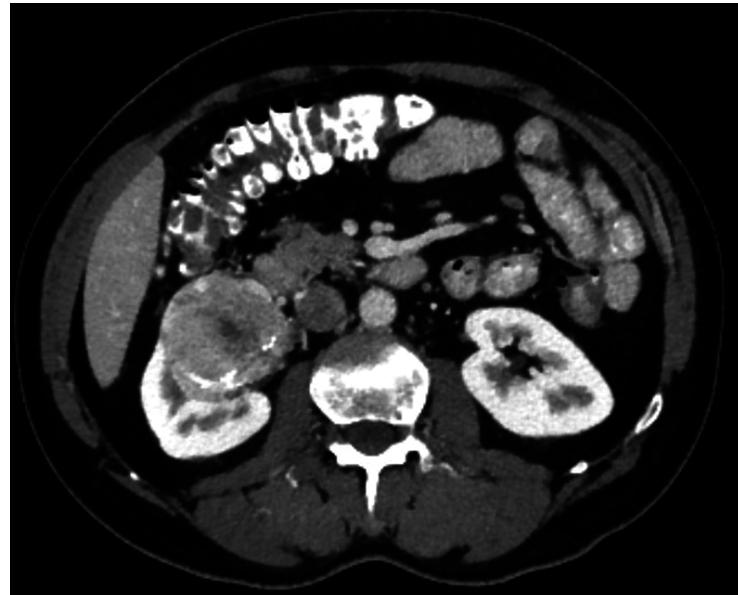

CASE PRESENTATION

The authors report a case of a 51-year-old male patient with renal cell carcinoma. During his evaluation, he seemed to have a lung mass which revealed to be a carcinoid tumour. As the patient had two primary malignancies, he was managed according to the treatment options for each tumour.

病例介绍

作者报告了一例51岁男性肾细胞癌患者。在对他进行评估期间,他似乎有一个肺部肿块,结果显示为类癌肿瘤。由于该患者患有两种原发性恶性肿瘤,因此根据每种肿瘤的治疗方案对他进行了处理。